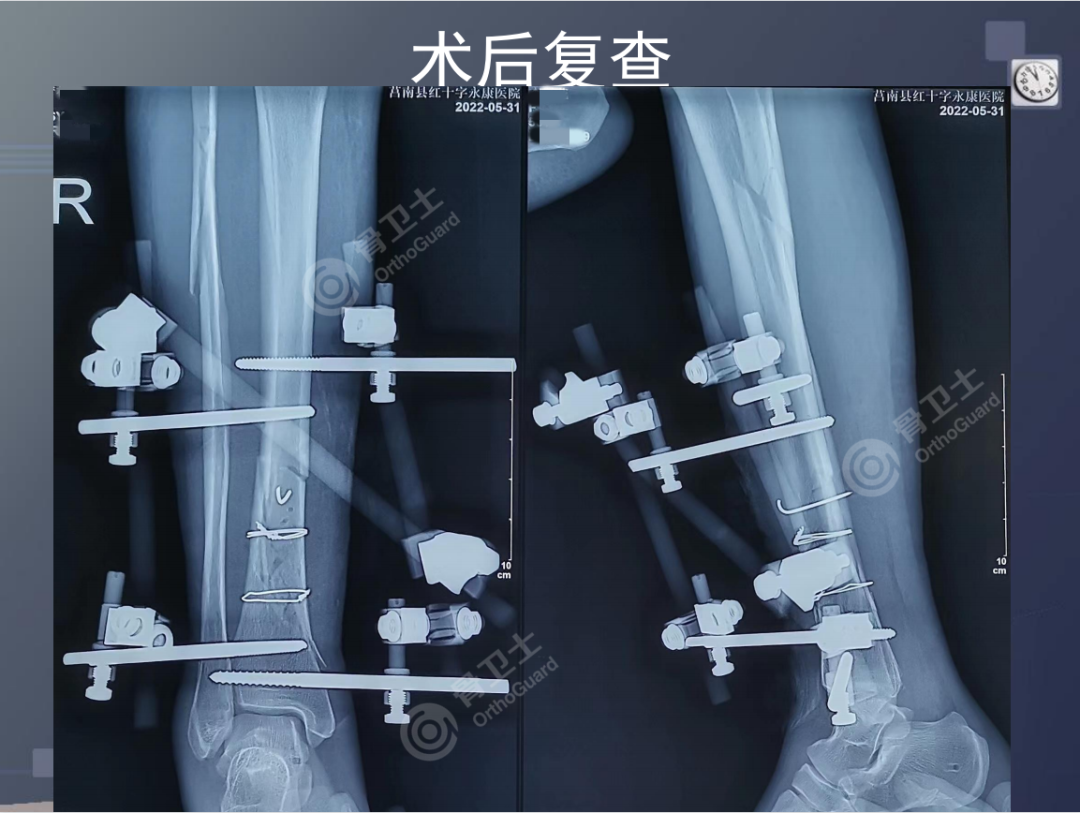

▲患者术后影像

陈强副院长介绍,该患者刚入院时,小腿肿胀明显,皮肤条件差,如急诊进行手术,可能出现术后小腿骨筋膜室综合症,有皮肤坏死可能。于是决定给予临时跟骨结节骨牵引术、局部冰敷及促进消肿药物治疗,入院第10天,小腿肿胀明显减退,行有限切开骨折处复位外固定架固定术。